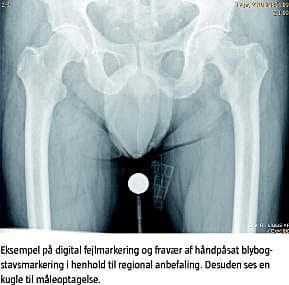

Alle optagelser i PACS - også optagelser som pga. fejleksponering er taget om - er inkluderet i undersøgelsens registrering. Brug af blænder på optagelser uden digital sidemarkering, som har medført, at den påførte blybogstavsmarkering ikke har kunnet aflæses entydigt, er inkluderet i kategorien manglende sidemarkering.

Sidemarkeringen af røntgenoptagelser hører med som et vigtigt standardelement i alle røntgenoptagelser, og i den nye regionale vejledning anbefales håndpåsat blybogstavsmarkering placeret så tæt på patienten som muligt, men i tilfælde af forglemmelse, eller hvis en særlig situation har umuliggjort håndpåsat blybogstavsmarkering, vil efterfølgende digital sidemarkering også være rigtig og skal være påført optagelsen, inden denne sendes til PACS.